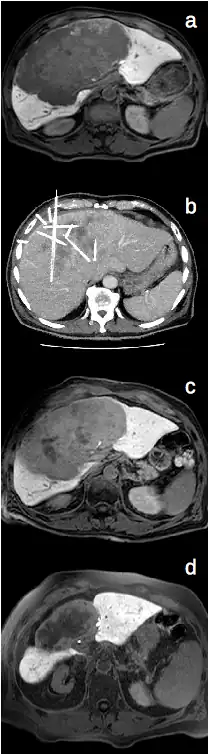

Die Anlage der Bestrahlungskatheter in die zu behandelnden Tumoren erfolgt zunächst über eine Punktion von außen, welche mit Hilfe der Computertomographie (seltener auch Magnetresonanztomographie oder Sonographie) durchgeführt wird. Hierbei erfolgt eine Lokalanästhesie im Bereich der Einstichstelle sowie zusätzliche Analgosedierung mit der Gabe von Schmerz- und Beruhigungsmitteln.

Nach Anlage und Befestigung der Bestrahlungskatheter wird der Patient in die Strahlentherapie verbracht und dort erfolgt über die Katheter die Hochdosisbestrahlung der Tumoren von innen mit einer Iridium-192-Quelle.